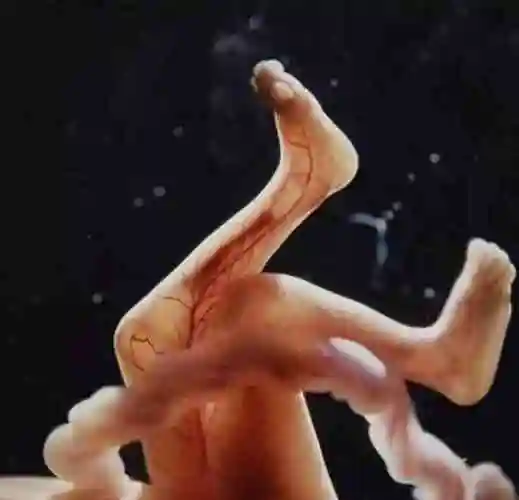

by lennart nilsson, 1965年 fetus, weeks(十八周的胎儿)